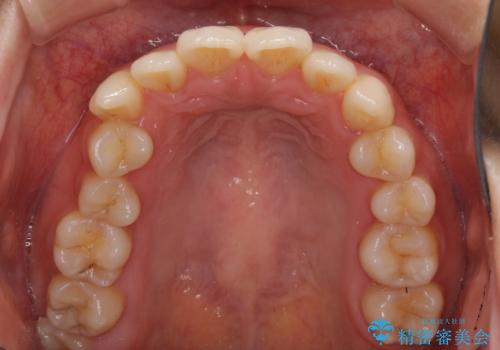

- 前歯のデコボコを気にして来院された患者様です。

叢生と捻転が随所に認められるものの、マウスピースで十分対応可能であったため、インビザラインにて矯正治療を行うこととしました。